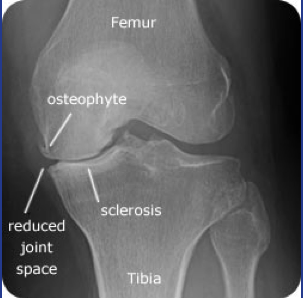

Osteoarthritis?

Degenerative bone disease

Features of osteoarthritis?

* Cartilage cracks (fibrillation) - reduced joint space

* Subchondral cysts

* Osteocytes - new bone formation at side

* Sclerosis